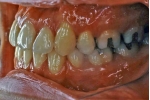

初診時